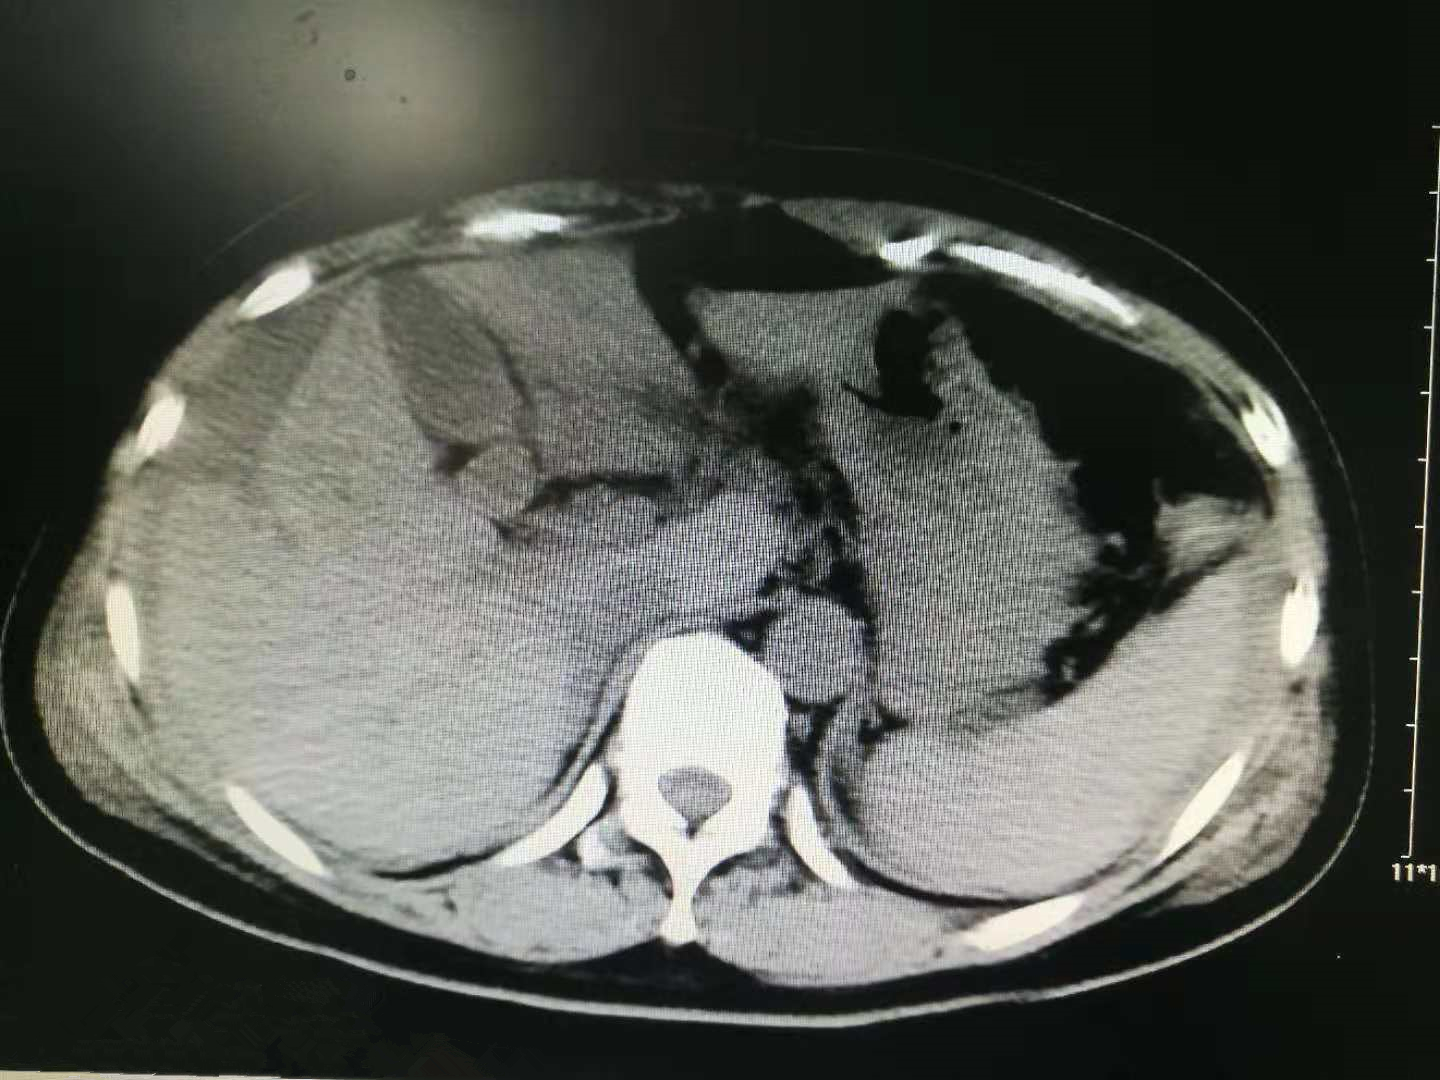

卢某某因胸腹部辗压伤入院,急诊以急腹症、多发复合伤收入普外一科住院治疗,伤后行CT检查:双侧多发肋骨骨折;肝脏损伤并腹腔大量积血;右肾挫伤;L1、2、3左侧横突骨折;T11、12左侧横突骨折。普外科李增德主任立即组织病例讨论、制定治疗方案,他分析道,患者其中一部分肝组织影像学上出现错层,突出肝脏表面,即使开腹手术,风险也非常高,预后难以预料,决定暂保守治疗。治疗期间给予腹腔置管引流,引出暗红色血性液体800ml,右胸腔置管闭式引流淡黄色反应性积液约1000ml,严密观察腹部及生命体征变化。经过20多天的治疗,患者病情稳定,胸腹腔积液消失,引流管已拔。精湛的医术和精心的护理使卢先生逐渐恢复了健康,在出院之际,特送上锦旗一面表示感谢。

影像资料